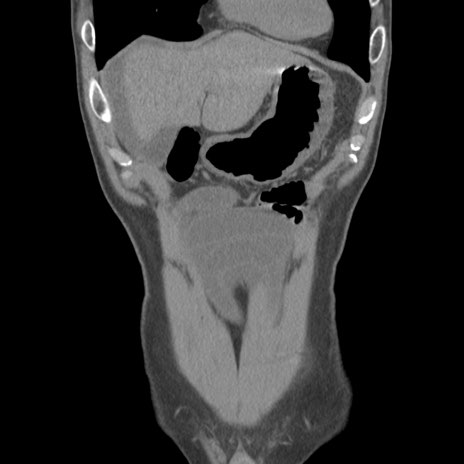

症例56 CT(冠状断像)

脂肪ウインドウ